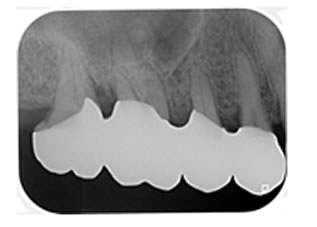

症例4

治療の特徴(患者I様)

初診時においては物を咬むと違和感が強く歯周外科処置を行いました。

骨のラインが部分的に増え、平坦にきれいに治っています。

2019年5月20日現在